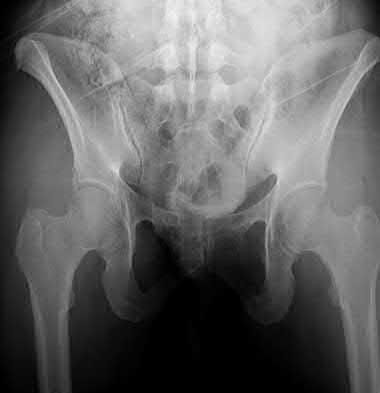

3. # Which of the following is not an appropriate implant for treatment of the fracture seen in Figure A?

5. Sliding hip screw Corrent answer: 5

The image shows a reverse obliquity intertrochanteric hip fracture.

According to the referenced article by Haidukewych et al, unstable peritrochanteric hip fractures have a worse outcome (failed in 9/16 cases) if treated with a sliding hip screw. Two additional factors that were found to have a strong correlation with postoperative failure (nonunion, loss of reduction) were poor reduction and poor implant placement. In this study, fixed angle devices were superior. Intramedullary fixation has the added advantage of a shorter lever arm and less potential for fracture collapse and limb shortening.

The IMN also acts as a medial buttress.

According to Sanders et al, the dynamic condylar screw (DCS) can also be used in subtrochanteric models, but should not be used if extensive comminution is seen, as they reported a high failure rate with DCS in these fractures if highly comminuted. They report a 77% overall union rate with this device.